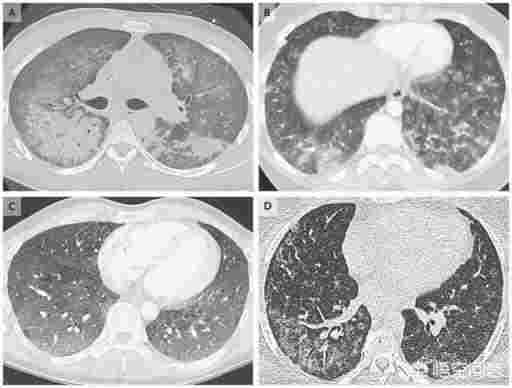

只能說這是一則非常抓人眼球的謠言。兩者最初被聯系起來是因為患者的X光片都可能出現白肺,也就是肺部浸潤性的炎癥。

但是白肺是多種肺炎共同的癥狀,并不能表明是什么引起了這個肺炎。電子煙肺炎和新冠肺炎不過從病因上還是癥狀上都存在許多區別。